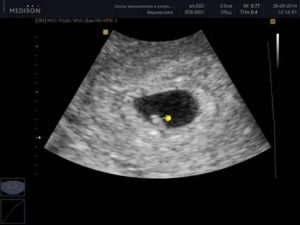

- Итак, приблизительно на 5-й неделе акушерского срока плодное яйцо уже должно быть видно в полости матки. Оно представляет собой небольшой пузырек размером около 18 мм. Иногда эти сроки могут чуть продляться, особенно у женщин с большой длиной менструального цикла. Однако в такой сомнительной ситуации пациентка должна оставаться на контроле у врача до окончательного установления диагноза «маточная беременность».

- Начиная приблизительно со срока 6 недель в пузырьке можно разглядеть контуры будущего зародыша, а иногда даже сердцебиение центрального сосуда – будущего сердца плода.

- Приблизительно с 7-й недели беременности и размера плодного яйца 25 мм зародыш должен иметь размеры около 5 мм и у него должно обязательно присутствовать биение сердца. Если эти критерии не соблюдаются, то есть основания поставить диагноз «замершая или неразвивающаяся беременность». Такое состояние подлежит динамическому ультразвуковому контролю через несколько дней, а также пациентке рекомендуют сдачу крови из вены на хорионический гонадотропин (ХГЧ) в количественном измерении.